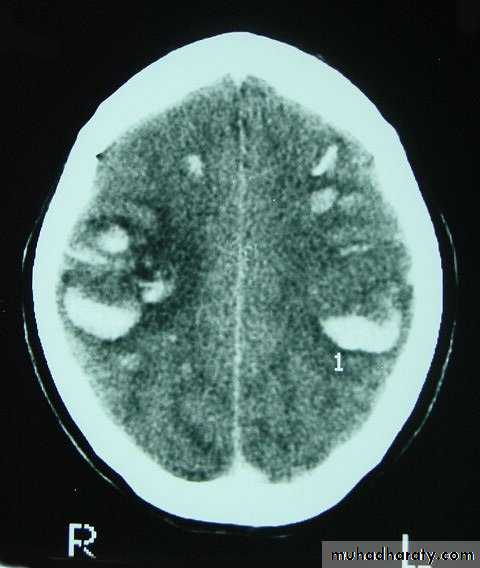

CT scans demonstrates contusions as small areas of haemorrhage in the cerebral parenchyma.

3. Cerebral Contusion

Resolution of Contusion